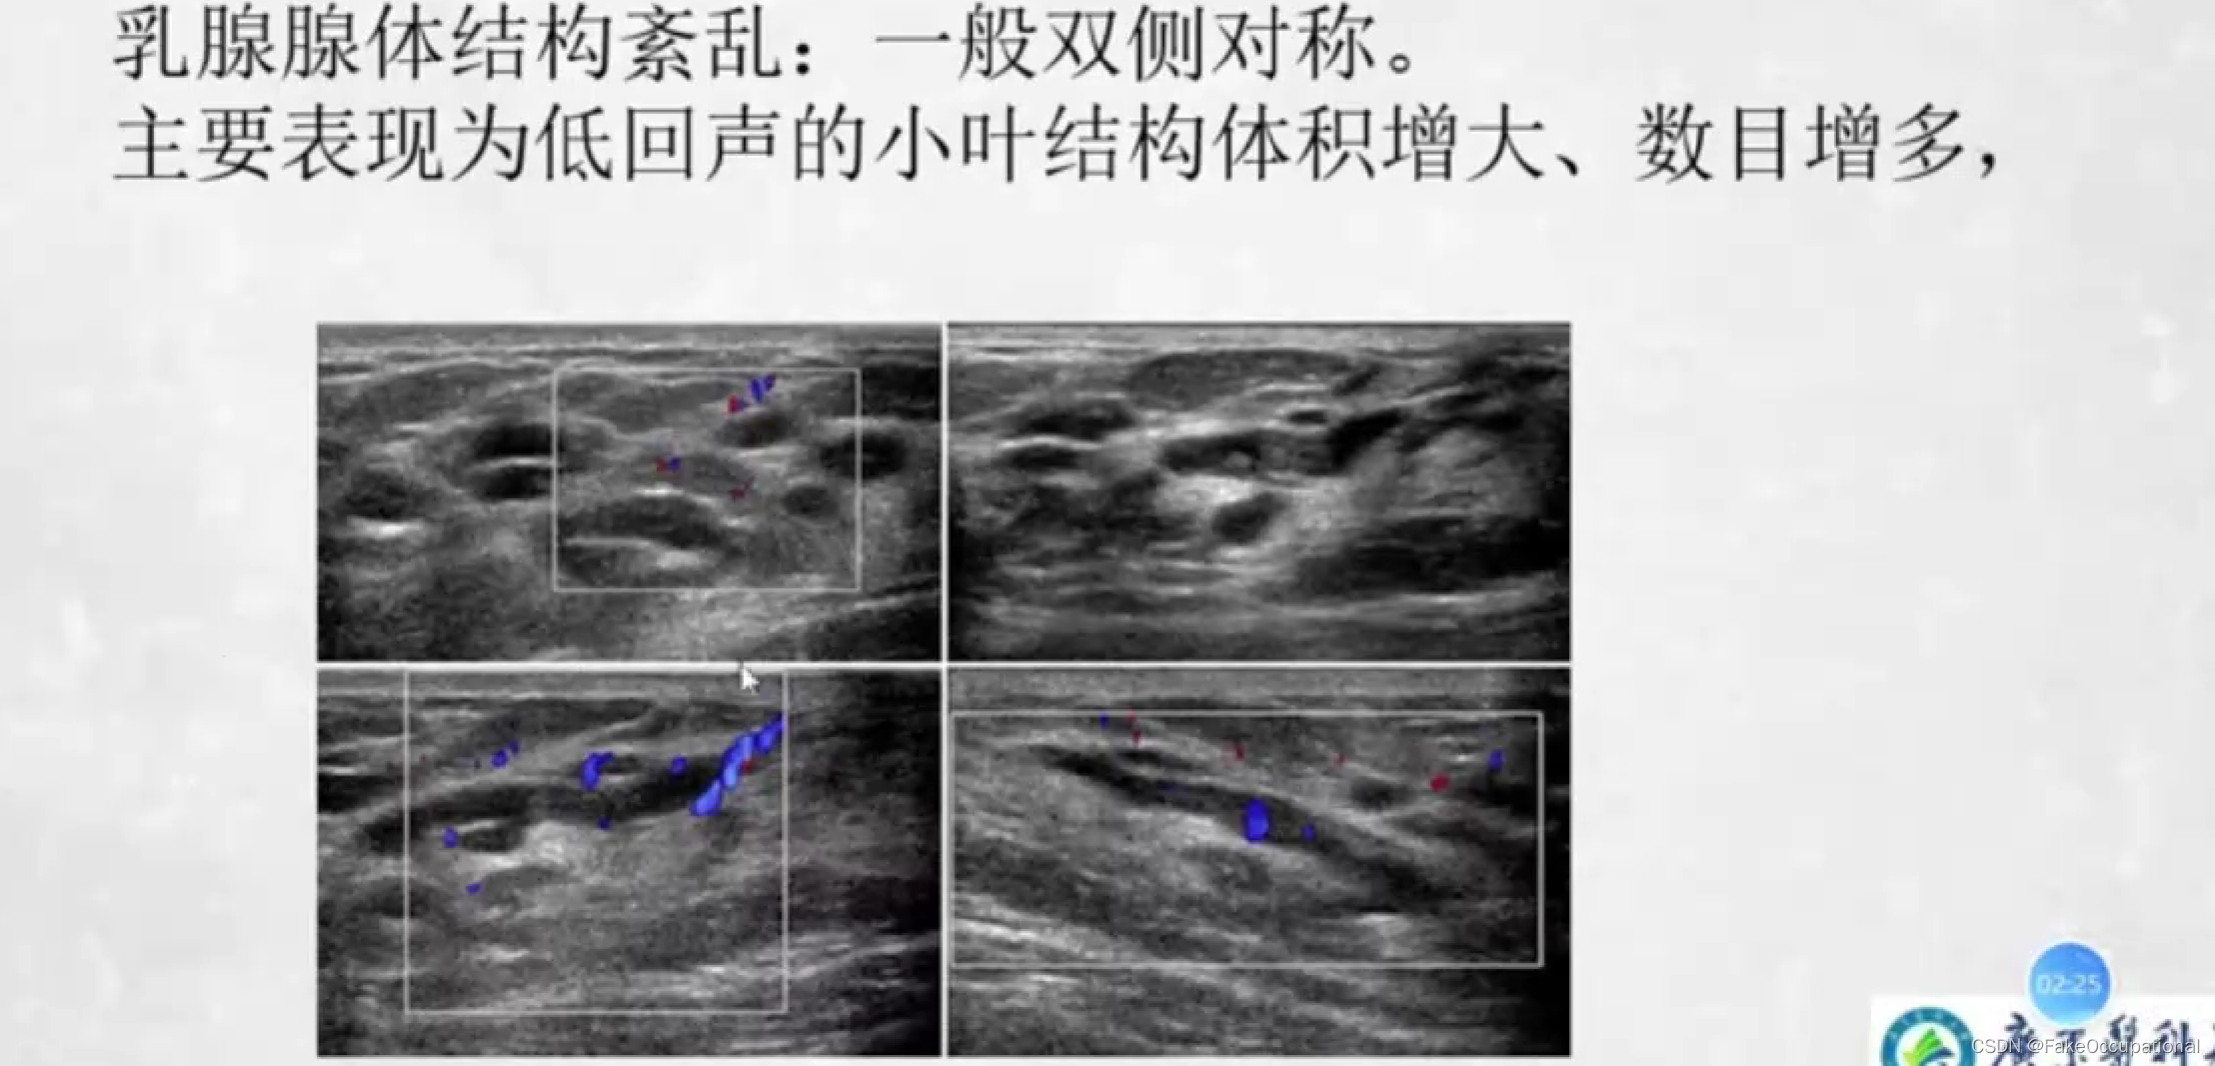

乳腺增生症

- 女性最常见的乳房疾病好发年龄为30一50岁与内分泌激素紊乱有关(尤其雌激素增高)

- 双侧乳腺周期性胀痛月经前3一4天疼痛加剧月经来潮后症状减轻

- 可触及多个大小不等的质韧结节多呈圆形或条索状